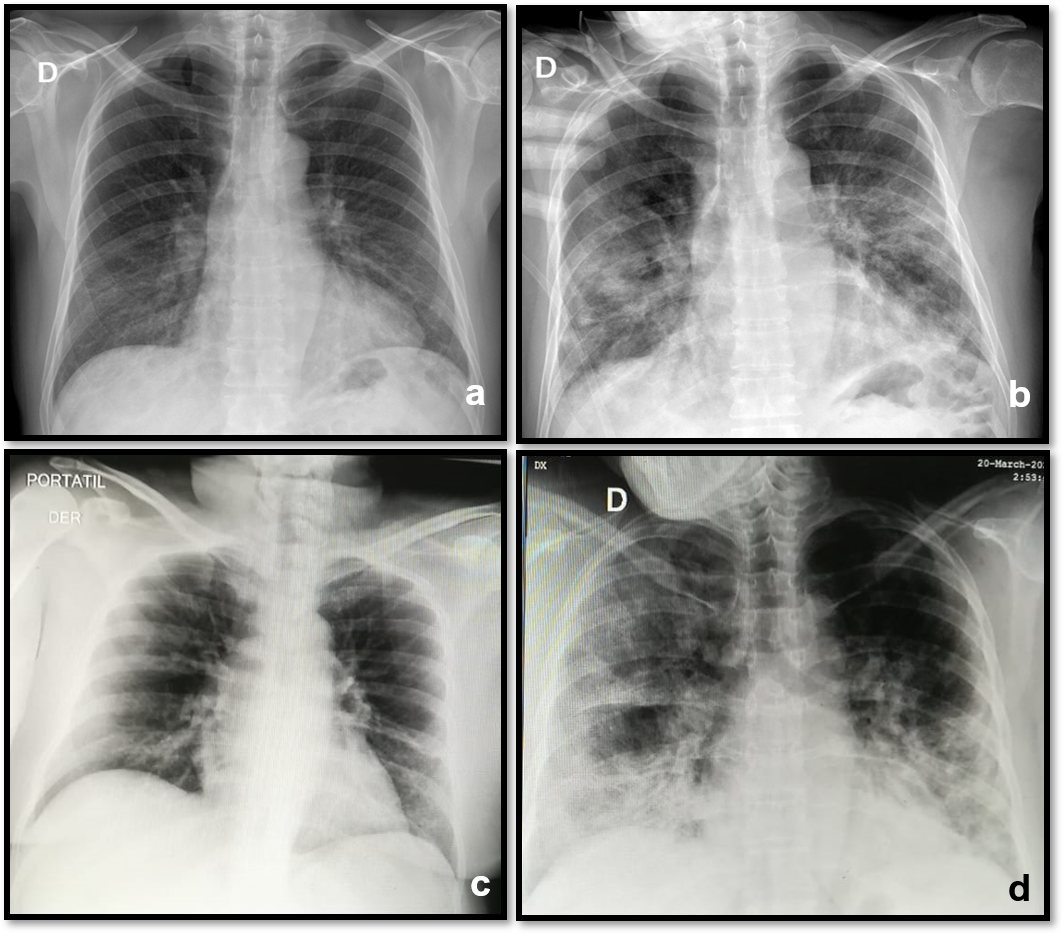

Chest x-rays were performed on 86 patients during the admission, all with bilateral opacity. None presented pleural effusion (Figure 1).

Figure 1 Chest x-ray with the evolution of two patients. a).- Male. 59 years old. March 25. At admission: Interstitial lung pattern in lower zones with right predominance. b).- March 31. in ICU: Right alveolar opacities in mid and lower zones Left hazy opacity in mid and lower zones. Dyspnea got worse and required invasive mechanical ventilation. Dies 14 days later. c).- Female. 59 years old. March 18. At admission: Lower vague hazy densities. d).- March 20. in ICU: Bilateral diffuse interstitial pattern with ground glass opacities in the right upper and lower areas. Greater lower right opacity due to peribronchovascular thickening. Dyspnea got worse and required invasive mechanical ventilation. She had a full recovery and was discharged 23 days later.